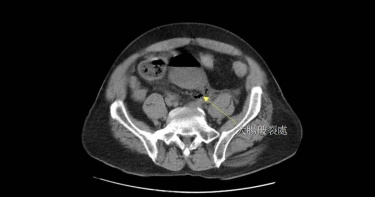

夫妻為孩子成績爭吵 下秒他胸痛噴汗送醫!檢查驚見「血管氣炸40cm」